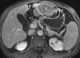

Urethritis cystica

Urethral filling defect